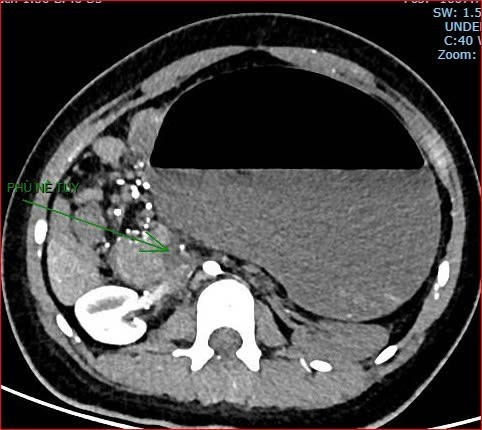

Khoảng 21 giờ 40 phút, kết quả chụp cắt lớp vi tính cho thấy tình trạng bệnh rất nặng và hiếm gặp, gồm: xoắn dạ dày, nhồi máu thận trái, nhồi máu lách, viêm đầu tụy, viêm hỗng tràng kèm dịch ổ bụng và tràn dịch màng phổi, trên nền bệnh nhân có hội chứng Down và tim bẩm sinh.

Hình ảnh chụp cắt lớp vi tính thể hiện tình trạng bệnh nhân rất nặng, hiếm gặp.